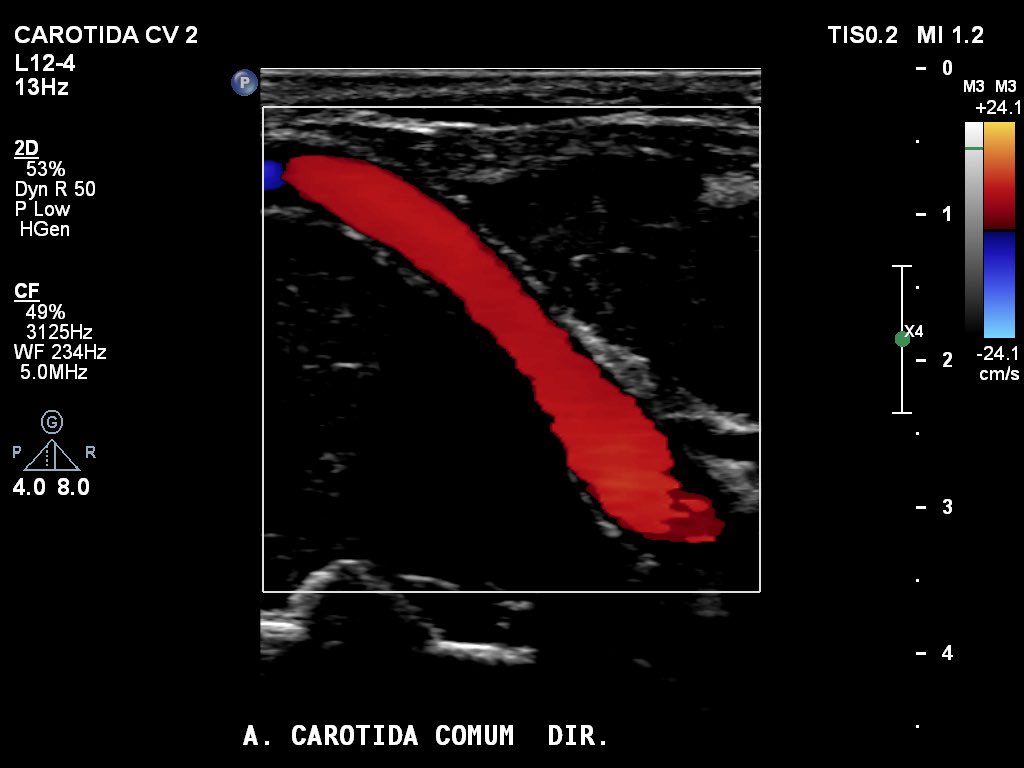

Solid cervical tumor surrounding the right common carotid artery, displacing it from its usual path.

#vascularultrasound